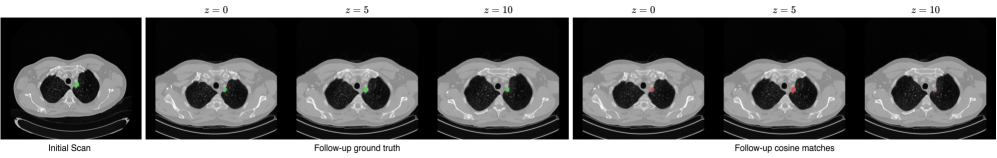

Refer to caption

Figure 2: Cosine similarity matching between lesion embeddings in an initial and a follow-up scan of the same patient. The first set of slices are ground-truth lesion segmentations across ten slices (zz); the second set shows the top-kk voxel matches between averaged lesion embeddings from the initial scan and all embeddings in the next.

Tracking disease progression, such as changes in tumor volume over time, represents a potentially critical clinical application of pretrained models. This approach involves extracting a model’s feature representation of a lesion from an initial scan and identifying the most closely related embeddings in subsequent scans. Ideally, features most relevant to the disease are consistently matched across follow-up scans. Figure 2 demonstrates that TAP-B-3D’s features could be sufficiently descriptive to locate a lesion from an initial scan in a follow-up scan of the same patient. It indicates that fine-grained information is indeed present in the embeddings; however, a quantitative analysis would be needed to draw conclusions.